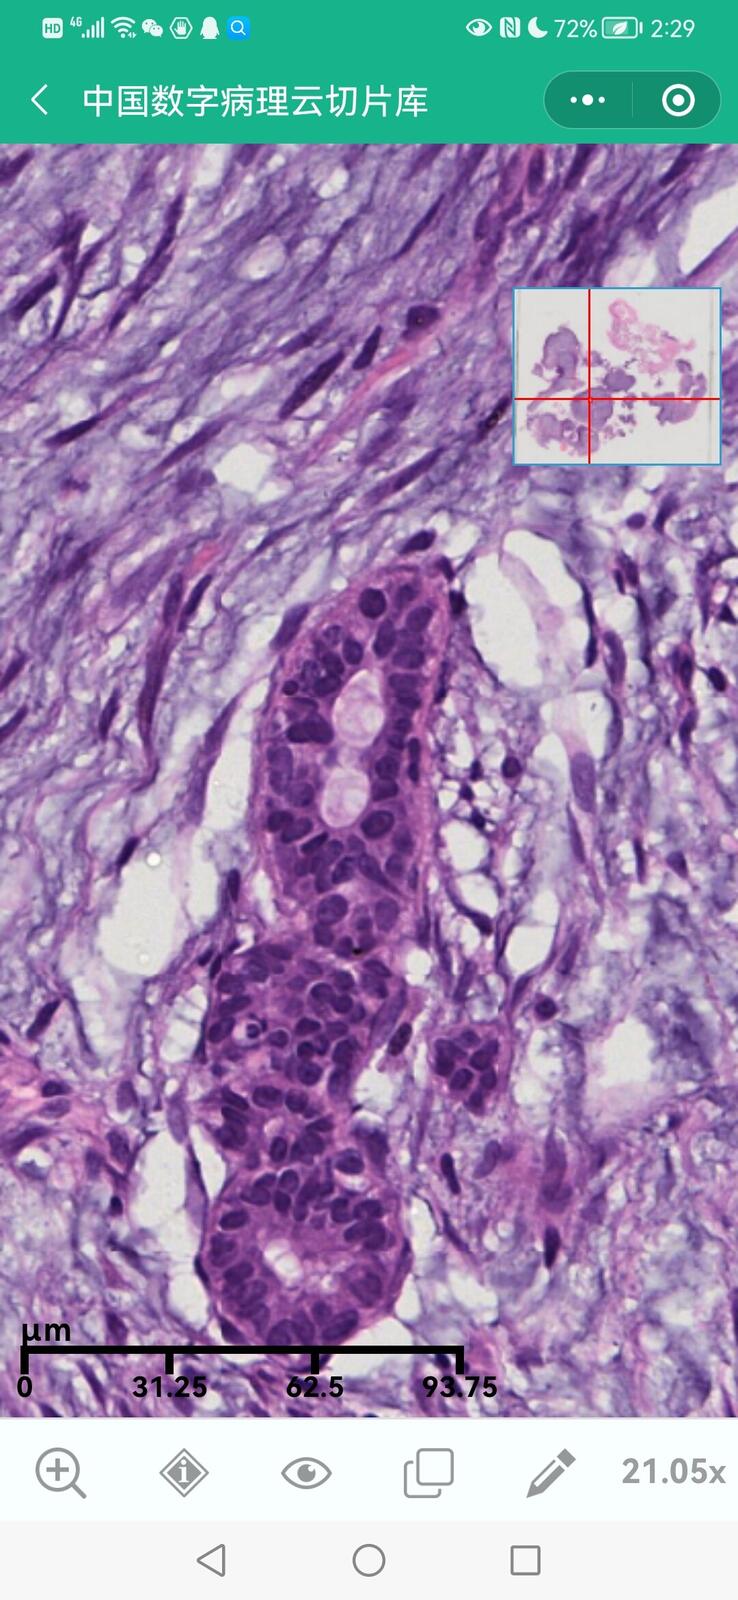

乳腺分泌性癌(29岁)